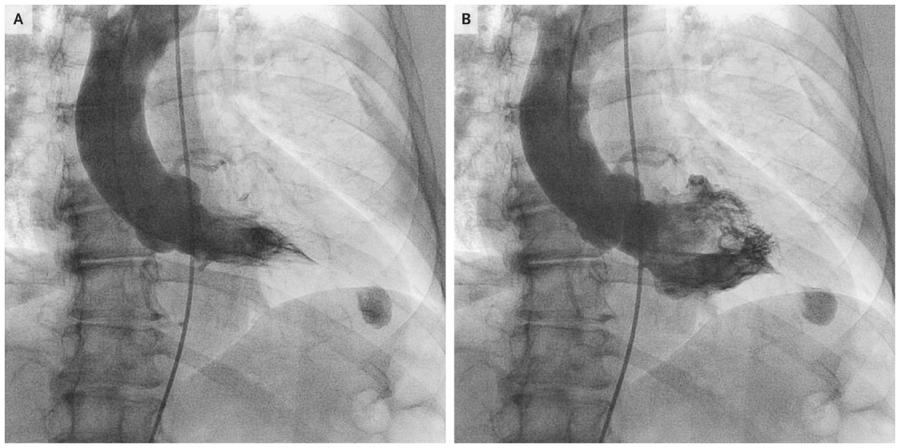

3. 左室造影:

对心尖肥厚型心肌病患者行右前斜30°左心室造影可见舒张期左心室呈特征性“黑桃样”形改变,心尖部心肌明显肥厚;

-

收缩期可见心尖腔部位完全闭塞。

似扑克牌“黑桃”形改变,尖部向右下